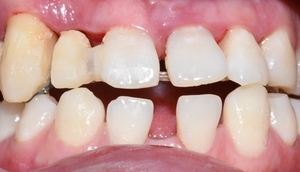

이번에는 앞니가 너무 벌어져서 보기싫던 20대 후반 남자 환자분의 변화 증례를 보여드리겠습니다.

환자분이 정보전달을 위해 공개에 동의하셨습니다! 감사합니다!

처음오셨을 때 상태이구요

아직 젊은 20대 분이신데도 X-ray상 어금니 쪽에 충치가 굉장히 많으셨고 잇몸뼈도 많이 녹아있는 상태였습니다.

여러 충치치료를 받으셨는데 환자분이 벌어진 앞니가 아무래도 신경이 쓰이셨던 모양이에요.

앞니가 벌어져 있다보니 발음도 많이 새는 상태이구요.

아래 앞니는 일반적인 분들보다 2개가 없는 상태였구요,

위 앞니 중에 화살표 된 치아는 굉장히 많이 흔들리는 상태였습니다.